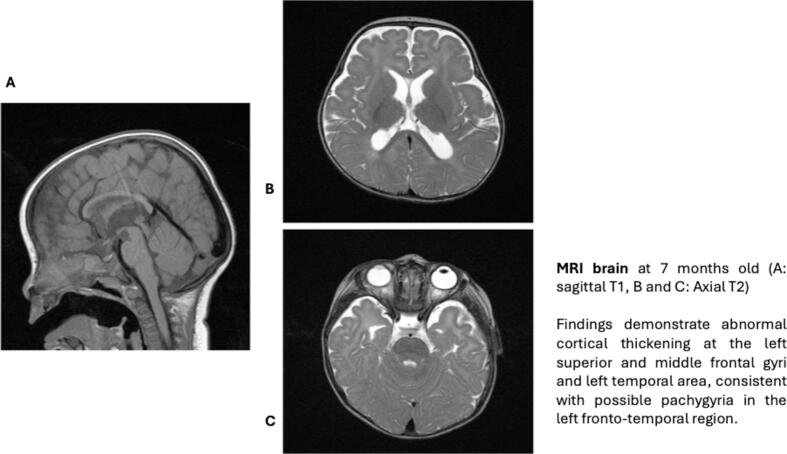

Dynein Cytoplasmic 1 Heavy chain 1 (DYNC1H1)-related disorders are a spectrum of conditions including neurodevelopmental disorders, congenital brain malformations, and neuromuscular diseases. These clinical features may co-occur, with four main disease entities including epilepsy with developmental epileptic encephalopathy such as infantile epileptic spasms syndrome (IESS) and Lennox-Gastaut syndrome (LGS), axonal Charcot-Marie-Tooth disease type 2O, spinal muscular atrophy with lower extremity-predominance (SMALED), and congenital cortical malformations. Epilepsy associated with this disorder often becomes drug-resistant and requires multiple medications and, in some cases, non-pharmacological treatments. To date, there is no specific epilepsy treatment that is particularly effective in this disorder. We report our experience in a case of a 3-year-old girl with a pathogenic variant in DYNC1H1 who presented with a developmental epileptic encephalopathy consistent with IESS and achieved seizure freedom on classic ketogenic diet (KD) after failing Adrenocorticotropic Hormone (ACTH), vigabatrin, and clobazam. The patient remained seizure free for more than 2 years on dietary monotherapy and had reported improvement in alertness, cognitive ability, muscle tone, and a normalized EEG. The ketogenic diet therapy, therefore, has shown to be highly effective in this case with DYNC1H1-related epilepsy.